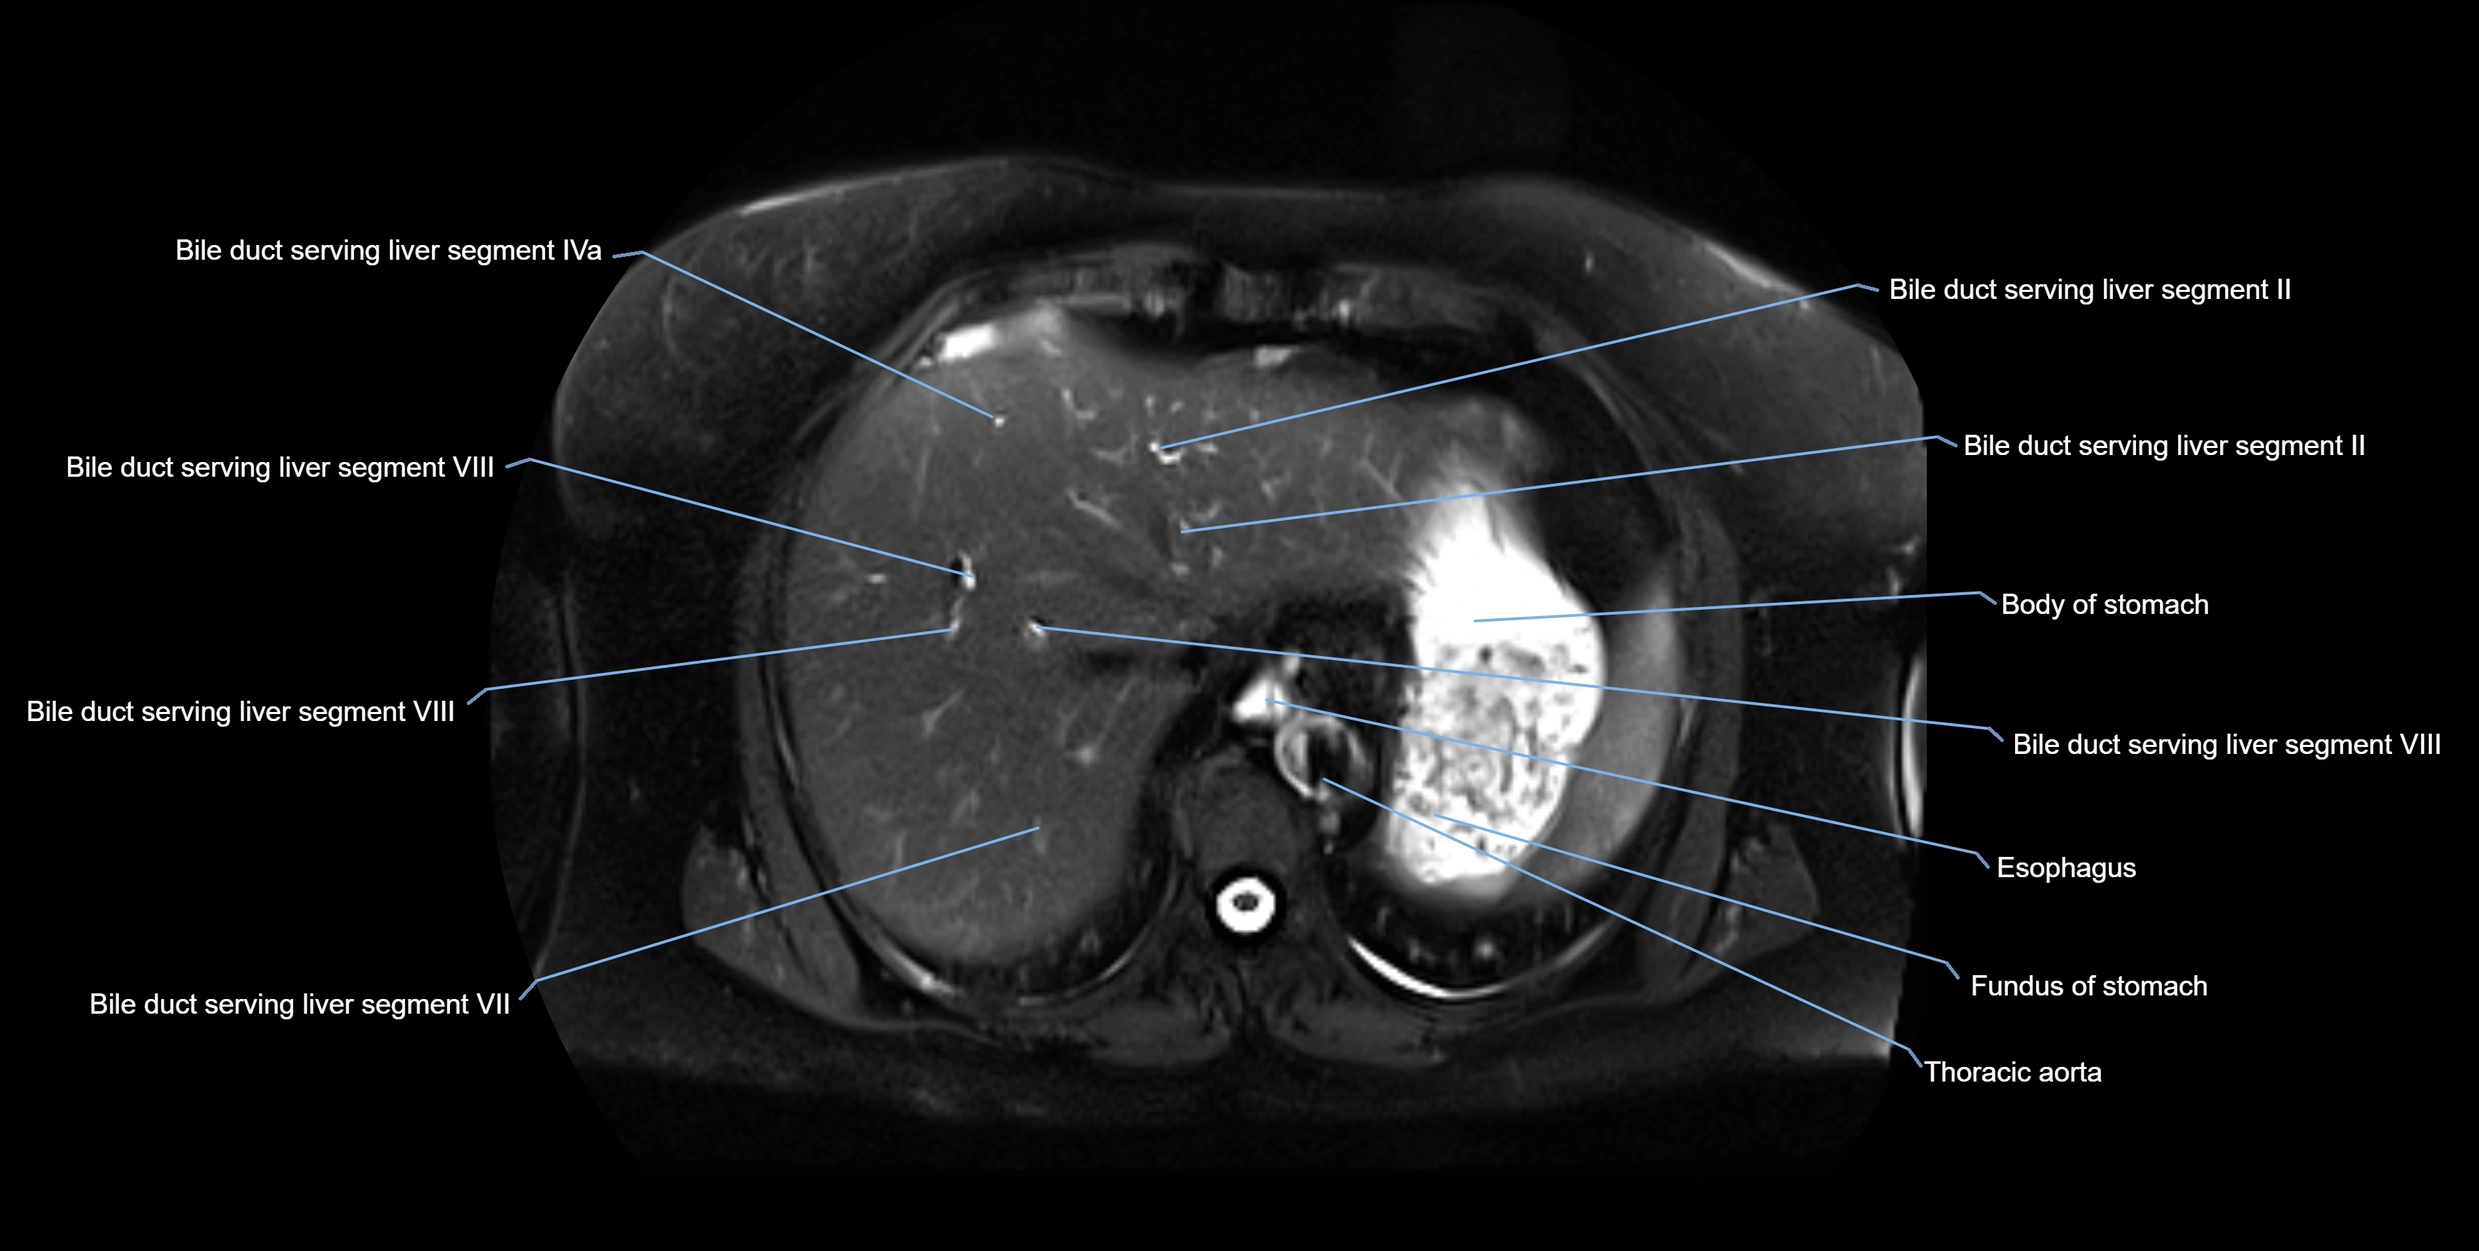

MRI image

image